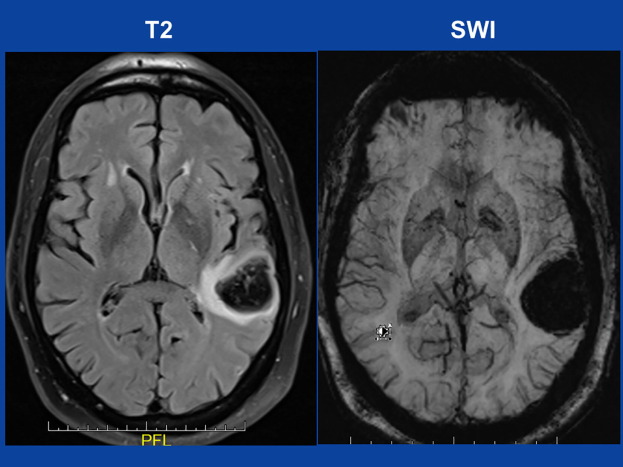

今回、新型コロナ遺伝子ワクチンの2回目接種7日後に脳内出血が起こった症例が報告されましたのでご紹介いたします(Aphasia seven days after second dose of an mRNA-based SARS-CoV-2 vaccine. Brain Hemorrhages In Press, Corrected Proof, Available online 24 June 2021)。

ワクチン接種7日後に、突然文字が読めなくなり、失語(motor aphasia with paraphasias)になりました。

入院後、左脳内出血が認められました。

入院時、高血圧(170/98 mmHg)および凝固系の軽度亢進が認められたようです(slightly elevated D-dimer)。

新型コロナ遺伝子ワクチンでは、脳血栓症が多く起こることが知られていますが、さらに脳内出血に進展する例も散見されます(Fatal cerebral haemorrhage afterCOVID-19 vaccine. Tidsskr Nor Laegeforen. 2021;29:141)。